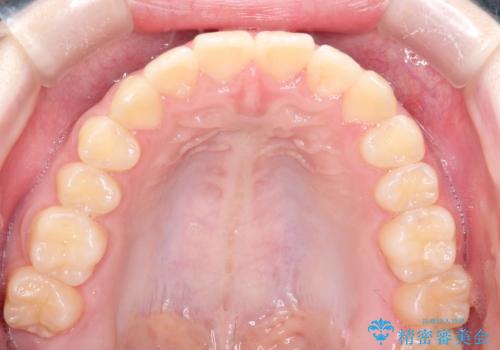

なるべく通院回数を減らして矯正したい インビザラインでのガタガタ矯正

ワイヤー矯正が1か月に1回程度来院が必要なのと比較すると、2-3か月に1回の来院でもよいので(症例によります)、通院回数を減らすことができて、患者様の負担を減らすことができます。